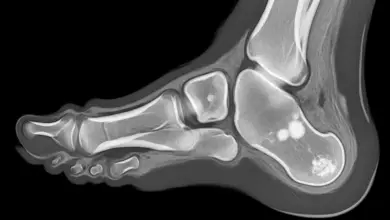

- Radiografia com carga: mostra redução do espaço, esclerose subcondral e osteófitos.

- Ressonância magnética: detecta edema ósseo e lesões de cartilagem em fases iniciais.

- Tomografia: útil para planejar osteotomias, artrodese ou prótese.